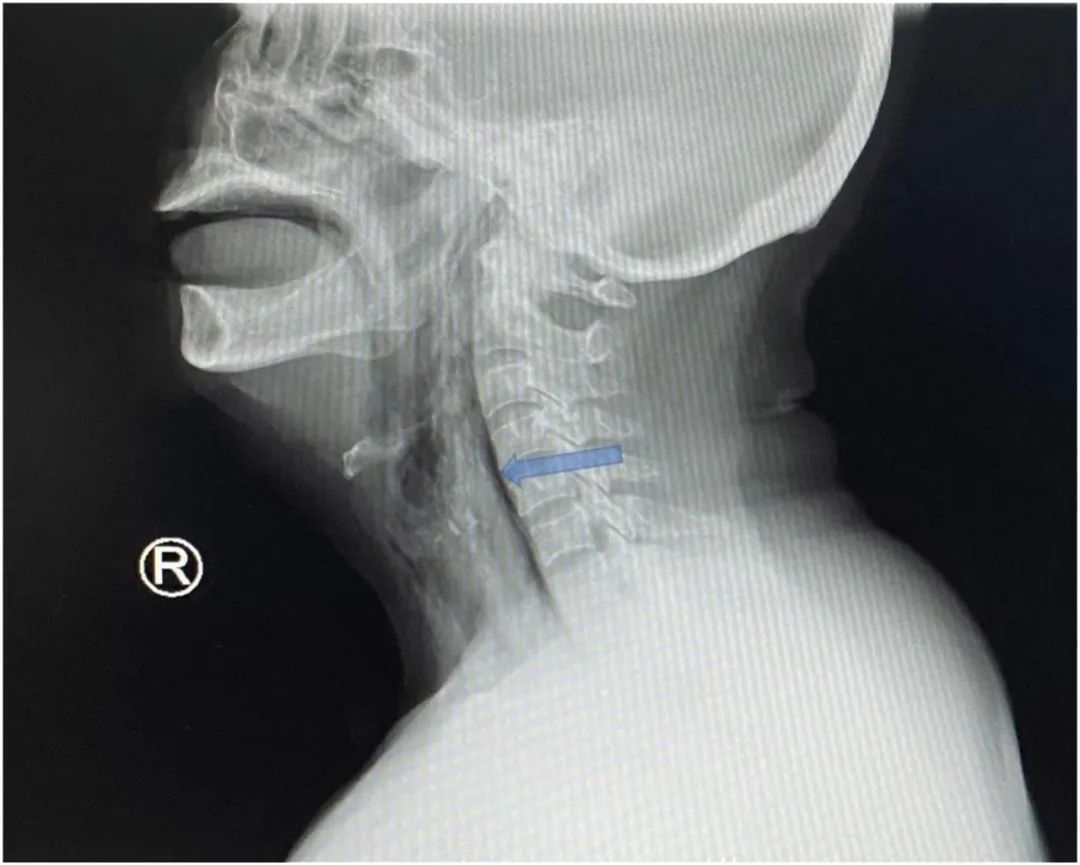

图片来源于The Journal of Emergency MedicineX光片找不到的鱼刺

喉镜检查没有发现。X光片也看不到。“这可能和鱼刺致密度低有关,在X射线下不易显像。”文章通讯作者、士拉央医院耳鼻喉头颈外科医生Athierah Muhammad称。

最终,CT在该女性的胸锁乳突肌上,扫描到一根5.1厘米长的异物。

图片来源于The Journal of Emergency Medicine胸锁乳突肌是颈部众多肌肉中最大最粗的一条,离食道、气管远远的。鱼刺是怎么过去的呢?